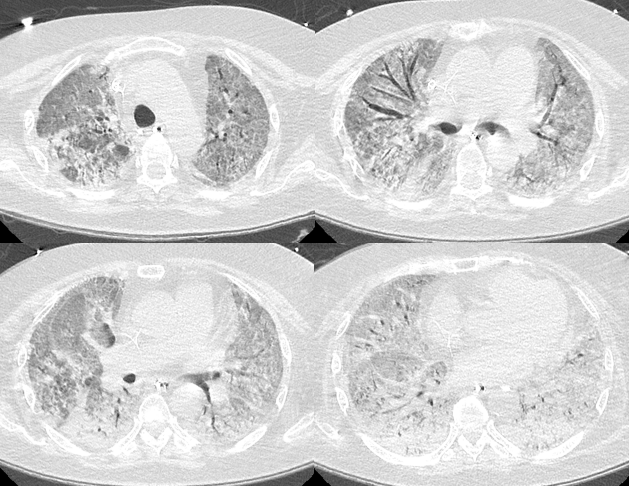

复查胸部CT

病变范围较前扩大,且出现气压伤、纵隔气肿。

图片